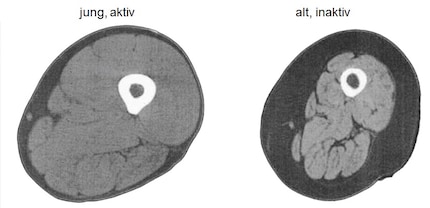

Les processus de vieillissement sont associés à des modifications ultrastructurelles telles qu'une augmentation du tissu conjonctif et une infiltration graisseuse (image) [29-31]. La surface non contractile était deux fois plus importante lors de la comparaison entre les hommes jeunes et âgés et pourrait donc mieux expliquer la perte de force observée que la réduction de la surface de section transversale de type II [31].

Images de résonance magnétique à travers le milieu de la cuisse d'un adulte sain de 25 ans (à gauche) et d'un adulte sain de 75 ans (à droite), montrant une sarcopénie. On remarque la masse musculaire plus faible (gris clair), la graisse sous-cutanée plus importante (gris foncé) et l'augmentation de la graisse intramusculaire (lignes gris foncé) dans la jambe du participant le plus âgé. Adapté de [32].